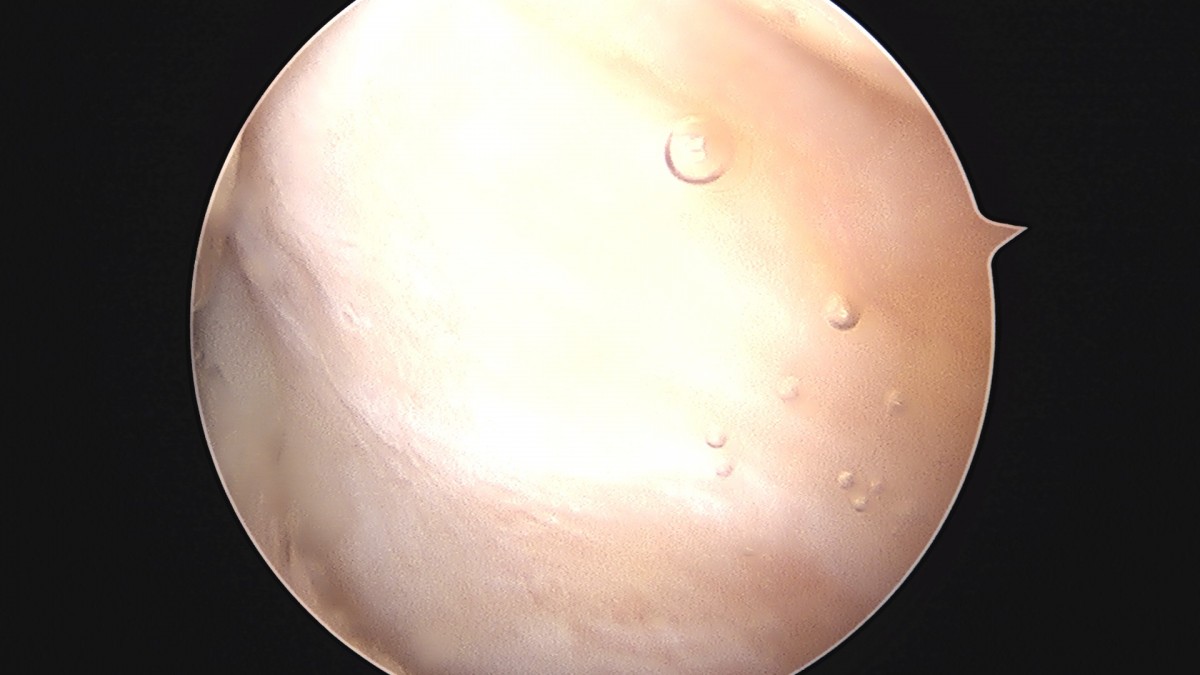

이재상원장님 무릎 반월상 연골판 절제술 강일O 환자

작성자 최고관리자 댓글 0건 조회 372회 작성일 25-09-16 16:12